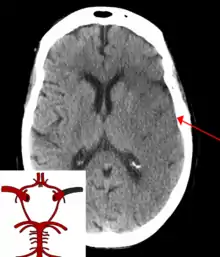

CT scan of the brain showing a prior right-sided ischemic stroke from blockage of an artery. Changes on a CT may not be visible early on.[1] | |

The biggest risk factor for stroke is high blood pressure.[7] Other risk factors include high blood cholesterol, tobacco smoking, obesity, diabetes mellitus, a previous TIA, end-stage kidney disease, and atrial fibrillation.[2][7][8] Ischemic stroke is typically caused by blockage of a blood vessel, though there are also less common causes.[13][14][15] Hemorrhagic stroke is caused by either bleeding directly into the brain or into the space between the brain's membranes.[13][16] Bleeding may occur due to a ruptured brain aneurysm.[13] Diagnosis is typically based on a physical exam and supported by medical imaging such as a CT scan or MRI scan.[9] A CT scan can rule out bleeding, but may not necessarily rule out ischemia, which early on typically does not show up on a CT scan.[10] Other tests such as an electrocardiogram (ECG) and blood tests are done to determine risk factors and rule out other possible causes.[9] Low blood sugar may cause similar symptoms.[9]